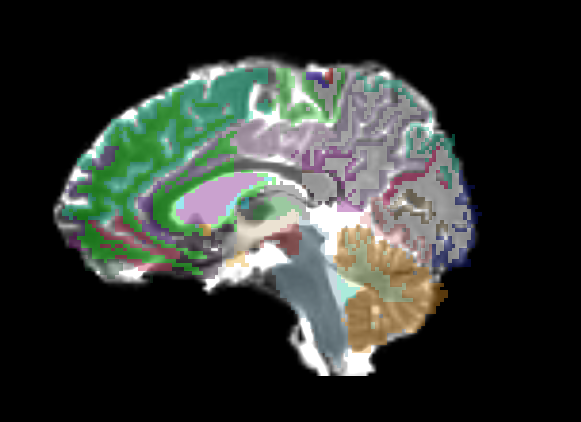

Freesurfer parcellation overlay

Only linear methods produce transforms that can be used to register a label map. Unfortunately, a linear registration can never account for the distortions of a DTI image, and as such there is no way to get a good registration of structural label maps to DTI space. In Slicer 2, I can create a transform node and do an automatic registration between two already created nrrds based on intensity via diff. demons or bspline, and then apply that transform to a label map, but I don't know of any way to get a similar transform in Slicer3.

Affine

The overlay has only a few places where it is usable, only in the center of ROIs you'll probably be in the same region on the DTI.

Linear

The overlay is useful in roughly the middle third of the brain, distortion of DTI means linear transform cannot match in the front or back of brain.

Archana's transform

Archana is an MIT grad student working on fMRI -> DTI registration. She used an affine transformation of some sort (I'm pretty sure it wasn't Slicer) to register a masked T2 to the masked DTI baseline, and transformed the freesurfer aseg the same way. You can see her registration has the same problems in the back of the brain, going beyond the borders of our image, but there is better registration in the front, matching up to the DTI distortion.